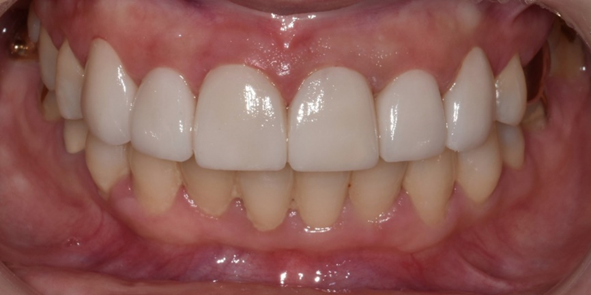

29세 여성

라미네이트 시술

(전) 2022-08-04 (후) 2022-08-12

치아 모양과 색상을 개선하고자 라미네이트 시술을 원하셨던 환자분입니다.

앞니 끝부분이 살짝 파절되셨고, 레진으로 떼워놓은 부분도 있어서 이를 제거하고 다듬은 후 라미네이트 시술을 진행했습니다.

라미네이트 완료 후 치아 모양과 라인이 전보다 고르게 개선된 것을 확인하실 수 있습니다.